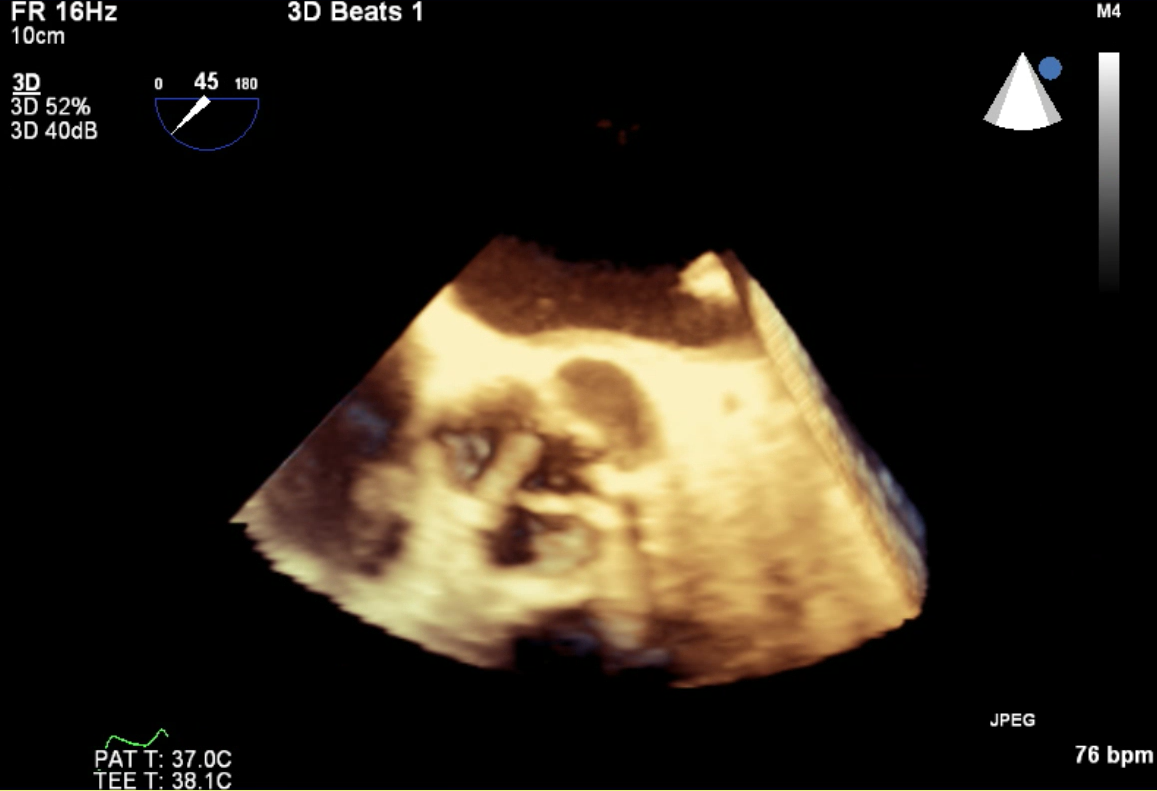

Pre-procedural electrocardiography showed a bifascicular block. Given the high surgical risk and concern for conduction disturbance, a 26-mm short-frame Sapien 3 valve was selected. Intracardiac echocardiography was used for real-time monitoring of valve position and anatomic relationships during implantation. The mean aortic valve pressure gradient measured by catheterization was 35.5 mmHg before valve deployment.

Under general anesthesia, arterial and venous access were obtained via the right femoral artery and vein. A temporary pacing lead was inserted for rapid pacing; however, consistent capture could not be achieved under fluoroscopic guidance. Therefore, intracardiac echocardiography (ICE) was advanced into the right heart to allow precise, close-range localization of the pacing lead. ICE was continuously used to provide real-time monitoring of valve positioning, implantation depth, and the spatial relationship between the transcatheter valve and the membranous septum. A 26-mm Sapien 3 valve was successfully deployed under temporary pacing. Post-deployment angiography and ICE confirmed optimal valve position without conduction disturbance, paravalvular leak, or other complications. The mean aortic valve pressure gradient decreased from 35.5 to 11.2 mmHg. The patient recovered uneventfully after the procedure.